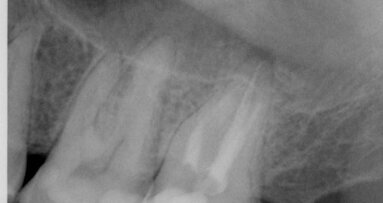

Une jeune femme de 21 ans, en bonne santé, nous a consultés pour un problème d’agénésie de l’incisive latérale gauche maxillaire. Elle avait suivi un traitement orthodontique durant trois ans au bout duquel l’orthodontiste n’avait pu obtenir qu’un espace mésio-distal de 4 mm entre le point de contact mésial de la canine supérieure gauche et le point de contact distal de l’incisive centrale gauche maxillaire. L’analyse de la radiographie périapicale numérique a montré qu’au-delà des six premiers millimètres sous le niveau de l’os crestal, 2,7 mm seulement séparaient les racines des deux dents, et après 8 mm, la distance n’était plus que de 2,1 mm (Fig. 2). Nous avons conseillé un second traitement orthodontique à la patiente, mais elle a refusé et nous avons donc discuté de la pose d’un implant étroit par la technique d’ouverture de l’espace inter-radiculaire. L’implant avait un diamètre de 3 mm, une longueur de suivantes : implant Press-Fit inséré dans l’ostéotomie ; design en plateau sans filetage ; épaulement incliné assurant un diamètre inférieur au niveau du col (selon le concept dit du « platform-switching ») ; positionnement sous-crestal à 1–3 mm sous le niveau de l’os crestal. La patiente a été anesthésiée par une injection d’articaïne et d’épinéphrine (Septocaïne, Septodont), et une légère incision crestale au moyen d’une lame de bistouri de 15c a été réalisée. Le foret-guide a été utilisé à une vitesse de rotation de 1 100 tr/min afin de perforer l’os cortical jusqu’à une profondeur approximative de 4 mm. Un alésoir manuel de Ø 2,5 mm puis un second de Ø 3 mm ont été utilisés pour effectuer pour ouvrir l’espace entre les racines.3, 4

Fig. 2 : Radiographie périapicale du site de l’agénésie de l’incisive latérale gauche maxillaire. L’espace entre les racines des dents 21 et 23 est toujours problématique après le traitement orthodontique.